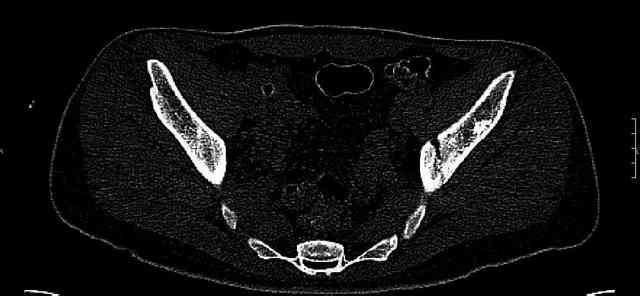

The joint is non-concentric as the head appears to be either "following the caudal segment", or the dome component is displaced from the tethered head... or so it seems... and he's young... so, many fracture surgeons would recommend reduction and fixation.

So we must decide preoperatively which part is the displaced segment?

It's difficult to know from these few selected images which component of the injury (was before and now) should be deemed the "soon to be mobile"

segment. It's my best guess that it is the caudal portion and there exists a healing fracture line somewhere thru the posterior column...one image

suggests it. If true, its early healing/union should be disrupted, and the resultant fragment mobility then allows accurate reduction.

Some more images. Does it help to guess which part of the acetabulum is displaced?

Normal appearing SI joints and a healed posterior column limb... my bet's on caudal segment displacement.